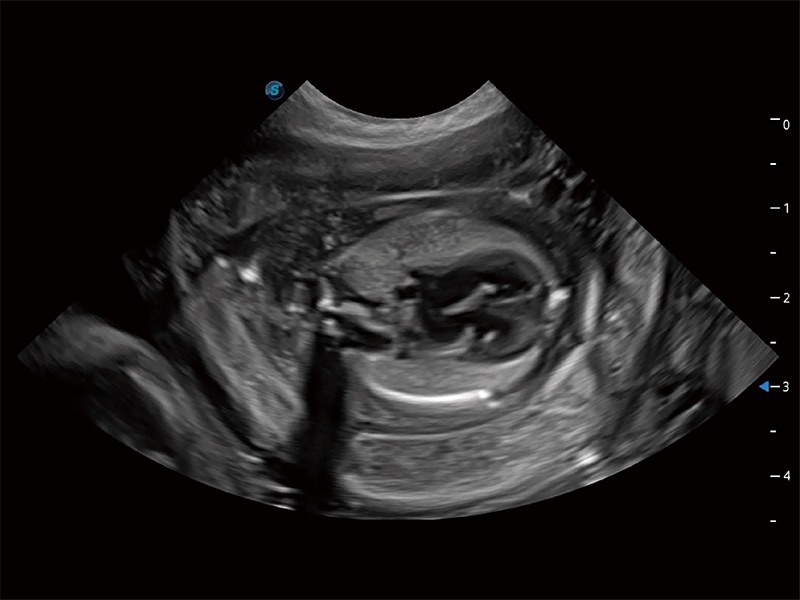

ProPet 80 全新的动物超声智能软件和丰富的探头群,为动物医生提供了高清晰度和精细分辨率的图像,无论在宠物、马科、畜牧还是实验室动物等应用中都可以轻松应对,为您的日常工作带来满意的体验。

动物是人类最亲密的朋友和最值得信赖的伙伴。乐玩lewin国际也一直致力于探索动物专用的超声影像解决方案。全新推出的ProPet系列,是乐玩lewin国际在动物超声影像智能化、专业化、精准化的一次跨越式革新。动物不能用言语来表述自己的不适,通过超声影像,ProPet系列搭建了动物医生与不同物种沟通的“桥梁”,为动物医生注入了“治愈之力”。 ProPet 80 是乐玩lewin国际匠心打造的一款高端动物专用彩超,采用性能卓越的全新硬件架构,极大提升超声系统的运行效率和数据处理能力,帮助动物医生从容应对日益增多的挑战性病例和日益多样化的临床需求。

ProPet 80 专为动物医生设计,对不同的动物体型和生理结构作出了针对性的优化。通过动物影像专用软件,可满足个性化的应用需求,帮助动物医生获得更精确的诊断数据。